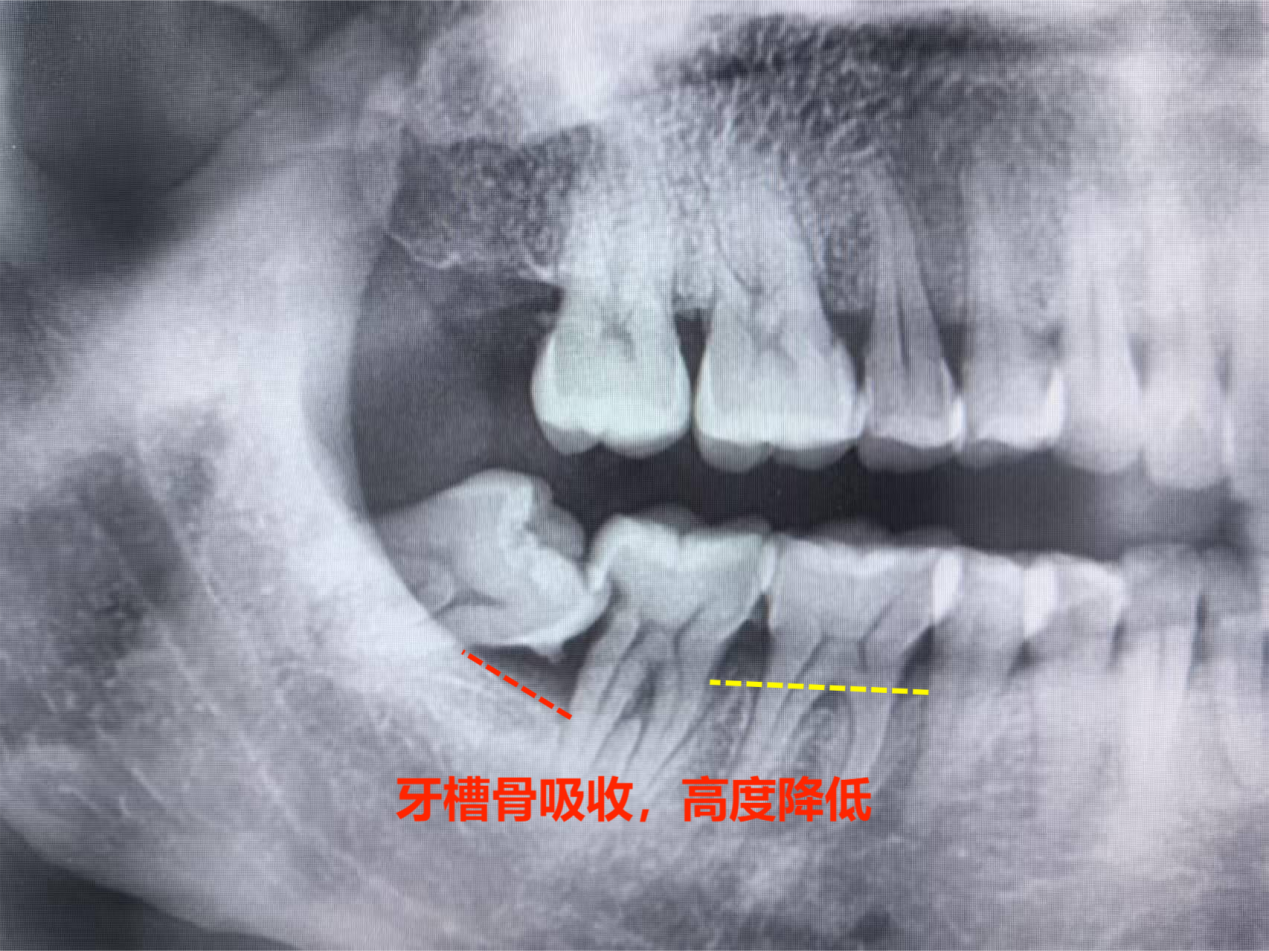

首先要明确核心结论:规范拔除智齿,绝不会导致其他牙齿松动!牙齿的稳固性依赖于牙根与牙槽骨的紧密结合,以及牙齿之间的相互支撑,而智齿的存在恰恰可能破坏这种平衡。智齿作为人类进化中逐渐退化的牙齿,多数人颌骨空间不足,导致智齿萌出位置不正、阻生,反而会持续挤压邻牙(尤其是第二磨牙),造成邻牙牙根吸收、牙槽骨破坏,久而久之才会让邻牙出现松动、移位。此时及时拔除智齿,是消除邻牙受压风险、保护牙齿稳固性的关键,而非导致松动的原因。

为什么会有“拔智齿致松动” 的误解?一方面,部分人拔智齿后短期内感觉邻牙有轻微 “浮动感”,这是因为手术中邻牙周围组织受到轻微创伤,出现暂时性水肿,并非牙齿本身松动,通常 1-2 周后会自行恢复;另一方面,若邻牙本身已因智齿挤压出现牙槽骨吸收,拔除智齿后,邻牙失去了智齿的“支撑点”,原本被掩盖的松动问题显现,让人误以为是拔牙导致,实则是智齿长期危害的结果。